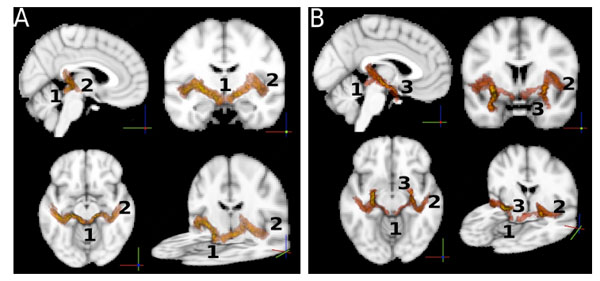

So far, statistics on the paths were computed independently on each single path between ROIs. For the sole purpose of visualizing the auditory paths as found by the probabilistic tractography, we used the intersection of the two paths (A→B, B→A) between any pair (A,B) of ROIs to define the location of a connection. For this purpose we normalized all the paths to the MNI template brain [45] using FLIRT [50], and averaged the per-subject results to obtain a group-wise connectivity map. The result is shown in Fig. (4). The paths in Fig. (4A) show connections between AC and IC. These paths also involve the MGB through which they pass. Note that the MGB was not used as a ROI. In Fig. (4B) we show the connections between the amygdala and the inferior colliculus, overlapped with the connections between the amygdala and the auditory cortex. The two paths follow the same route from the AM to the MGB, where they split into two separate paths, one to the IC and one to the AC.

A: Connections of the auditory pathways. Each path shown is the group average of the normalized (to the MNI standard template) paths of all the subjects. The intersection of two paths (A → B, B → A) between any pair (A,B) of ROIs was used to define the location of a connection. The image shows iso-probability surfaces, coded with color (the color scale ranges from yellow to red, where yellow indicates the highest probability to find the path in that brain region, and red indicates lower probabilities). Track endpoints are identified by numbers. 1: inferior colliculus, 2: auditory cortex, 3: amygdala. The iso-probability surfaces are semitransparent so that an exploration of all voxels is possible. B: the connections between the amygdala and the inferior colliculus, overlapped with the connections between the amygdala and the auditory cortex. .